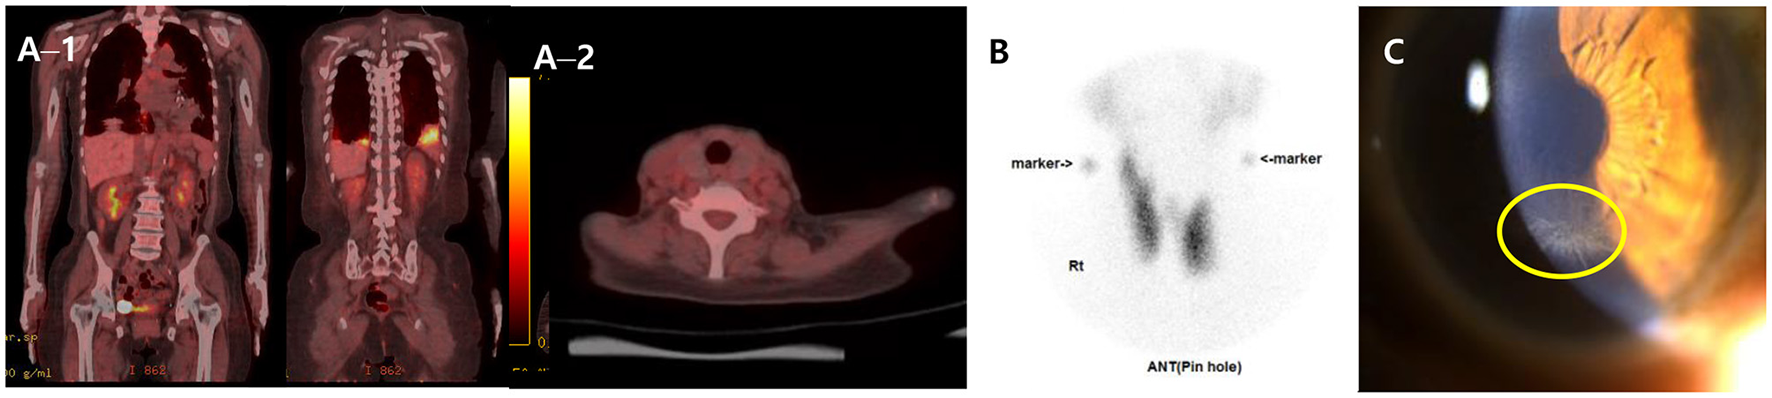

Further, to assess the possibility of amiodarone-induced thyroid dysfunction, we examined thyroid function tests. The thyroid-stimulating hormone level was less than 0.008 uIU/mL (reference range, 0.55–4.78), free thyroxine was 4.67 ng/dL (reference range, 0.89–1.76), triiodothyronine was 1.27 ng/mL (reference range, 0.6–1.81), thyroid binding inhibitor immunoglobulin (TBII) was 18.3 IU/L (reference range, 0–1.5), anti-microsome antibody was 139.0 U/mL (reference range, 0–60), and anti-thyroglobulin antibody was 125 U/L (reference range, 0–60). The PET–CT scan of the thyroid showed no metabolic lesion (Figure 3A). The thyroid scan (technetium-99 m pertechnetate scintigraphy) showed diffuse homogenous intake of technetium-99 m pertechnetate in both thyroid lobes (Figure 3B). Anti-microsomal antibody and anti-thyroglobulin antibody may be detected in Graves' disease (anti-microsomal antibody: 69.2%, anti-thyroglobulin antibody: 23–30%) (20); furthermore, with the results of TBII and the thyroid scan results, we diagnosed our patient as having type 1 amiodarone-induced thyrotoxicosis, a form of iodine-induced hyperthyroidism caused by excessive, uncontrolled biosynthesis of thyroid hormone by autonomously functioning thyroid tissue in response to iodine load, which typically develops in underlying latent Graves' disease (21). After consultation with the endocrinology department, methimazole (20 mg for 17 days followed by 5 mg/d) was used as treatment to manage excessive thyroid hormone synthesis.

Figure 3

FDG PET–CT, Thyroid scan and ophthalmologic exam. (A) FDG PET–CT scans of the whole body (A−1) and the thyroid (A−2) showing multiple hypermetabolic lesion in both lungs and no metabolic lesion in other organ including the thyroid. (B) Thyroid scan (technetium-99 m pertechnetate scintigraphy) presenting diffuse homogenous intake of technetium-99 m pertechnetate in both thyroid lobes. (C) Slit-lamp biomicroscopy showing numerous dense gray granular lines forming vortex patterns radiating from a median point at the junction of the middle and lower thirds of the cornea. FDG, fluorodeoxyglucose; PET–CT, positron emission tomography–computed tomography.

The patient persistently complained of blurred vision, and the ophthalmologic exam detected bilateral symmetrical corneal deposits in a vortex pattern (Figure 3C), which was compatible with amiodarone-induced vortex keratopathy.